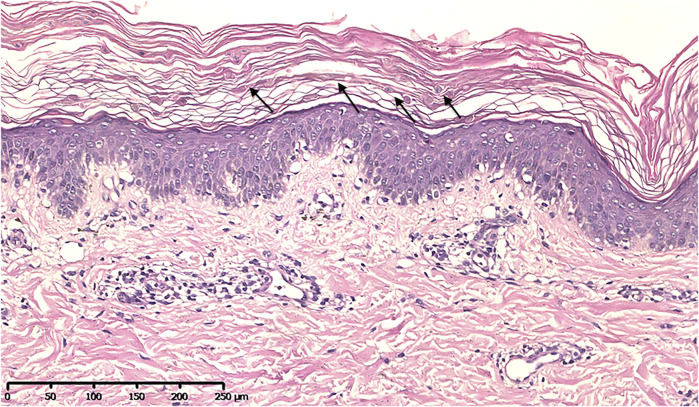

皮膚活檢顯示顆粒層細(xì)胞顯著增多,伴有角化不良,棘層肥厚和輕度表淺血管周圍淋巴細(xì)胞浸潤(見圖3),符合 變異性紅斑角化癥(EKV)的病理特征。

變異性紅斑角化癥佳學(xué)基因強

圖3:組織病理學(xué)圖像顯示顆粒層中有許多伴有角化不良的顆粒細(xì)胞、棘層肥大、乳頭狀瘤病以及輕度淺表血管周圍淋巴細(xì)胞浸潤(H&E)。